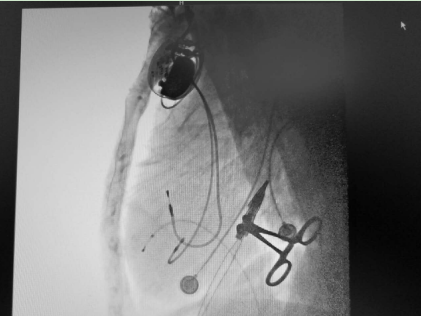

3天后成功植入心臟永久起搏器——熬過(guò)了前面的生死難關(guān),3天后,朱彬?yàn)槔先藢?shí)施了雙腔心臟永久起搏器植入術(shù),并程控相關(guān)參數(shù)以滿足患者個(gè)體狀態(tài)所需,手術(shù)過(guò)程順利,疾病得到根治。7天后,老人康復(fù)出院,出院后長(zhǎng)期門(mén)診隨訪未再出現(xiàn)暈厥,生活能夠自理。

起搏器成功植入